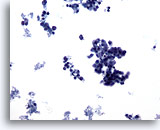

画像 3:肺FNA、肺大細胞癌 腫瘍細胞は、このシート内に見られる数個のアポトーシス細胞より大型です。細胞質の保存状態は良好であり、量が中程度で密度が高く、微細な空胞化が見られます。扁平上皮への分化の特徴である細胞間橋を思わせる細胞変化が局所的に見られます。核は円形から卵円形を呈し、結合性が疎のクロマチン集塊および肥厚化した滑面核膜が認められます。核小体は目立ち、不整形を呈し、単個から複数個見られます。高いN/C比を示します。

60倍

画像 3

肺FNA、肺大細胞癌

腫瘍細胞は、このシート内に見られる数個のアポトーシス細胞より大型です。細胞質の保存状態は良好であり、量が中程度で密度が高く、微細な空胞化が見られます。扁平上皮への分化の特徴である細胞間橋を思わせる細胞変化が局所的に見られます。核は円形から卵円形を呈し、結合性が疎のクロマチン集塊および肥厚化した滑面核膜が認められます。核小体は目立ち、不整形を呈し、単個から複数個見られます。高いN/C比を示します。

60倍